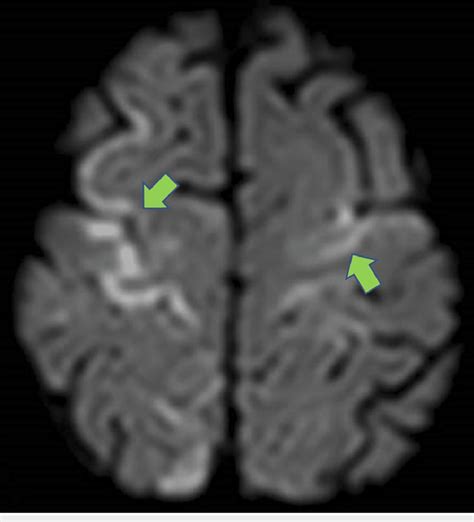

Now, let’s talk about where the rubber meets the road – the clinical applications of Diffusion-Weighted Imaging (DWI) . This technique has revolutionized how we diagnose and manage a variety of medical conditions, particularly neurological ones. The undisputed champion application for DWI is the early detection of acute ischemic stroke . When blood flow to the brain is cut off, brain cells begin to die within minutes. This cell death causes a rapid influx of water into the cells, leading to cytotoxic edema and restricted diffusion. DWI is incredibly sensitive to this restriction, allowing clinicians to identify a stroke within minutes of symptom onset , often long before it’s visible on conventional MRI sequences like T1 or T2. This early detection is absolutely critical because it allows for timely administration of clot-busting medications (thrombolytics) or other interventions, which can significantly improve patient outcomes and reduce long-term disability. It’s like catching a fire when it’s just a spark instead of a raging inferno! But DWI’s utility doesn’t stop at stroke. It’s also invaluable in diagnosing and characterizing brain tumors . DWI can help differentiate between different types of tumors, assess tumor aggressiveness, and monitor response to treatment. For example, some aggressive tumors have areas of restricted diffusion due to high cellularity. Furthermore, DWI plays a key role in evaluating traumatic brain injury (TBI) . It can detect subtle areas of injury, such as diffuse axonal injury (DAI), which might be missed on standard imaging. It helps in understanding the extent of damage and guiding management strategies. Beyond the brain, DWI is also finding increasing applications in imaging other parts of the body. In liver imaging , it can help detect and characterize liver lesions, assess liver fibrosis, and monitor treatment response in conditions like hepatocellular carcinoma. In prostate imaging , DWI is crucial for detecting and localizing prostate cancer, improving the accuracy of biopsies and treatment planning. Even in cardiac imaging , DWI is being used to assess myocardial infarction (heart attack) and monitor heart tissue viability. The versatility of DWI is truly remarkable, offering diagnostic power across a wide spectrum of clinical scenarios. It’s a testament to how understanding the fundamental movement of water can lead to profound clinical insights.

Interpreting Diffusion-Weighted Imaging (DWI) scans can seem a bit daunting at first, but once you understand the basic principles, it becomes much clearer. The most critical thing to remember is that restricted diffusion appears bright on DWI images . Why bright? Because the sequence is designed to attenuate the signal when water diffuses freely, and preserve the signal when diffusion is restricted. So, areas where water molecules can’t move easily – due to swollen cells, tightly packed structures, or other microstructural changes – will stand out as hyperintense, or bright, spots. The most classic example is an acute ischemic stroke . In the early minutes to hours after a stroke, brain cells become damaged, their cell membranes lose integrity, and water rushes in, causing them to swell. This swelling severely restricts the movement of water molecules. Consequently, the affected area lights up brightly on the DWI scan. This is often the very first sign of a stroke visible on MRI. However, it’s crucial to distinguish true restricted diffusion from other phenomena that can also cause bright signals. One important consideration is T2 shine-through . Some tissues naturally have a long T2 relaxation time, meaning they appear bright on conventional T2-weighted images. If these tissues also have some degree of diffusion, their signal might still appear bright on DWI, even if diffusion isn’t truly restricted. This is where the ADC map comes in as your best friend. Remember, the ADC quantifies the actual rate of water diffusion, independent of T2 effects. In areas of true restricted diffusion (like a stroke), the ADC values will be low . In contrast, areas that are bright on DWI due to T2 shine-through will have normal or even high ADC values. So, the combination of a bright DWI signal and a corresponding low ADC value is the hallmark of restricted diffusion and strongly suggests a pathological process like stroke or cytotoxic edema. Another important interpretation point is anisotropy . In tissues like the white matter of the brain, water diffusion isn’t the same in all directions. It tends to follow the direction of the nerve fibers. Multi-directional DWI and ADC tensor imaging can reveal these directional differences, which are crucial for understanding the integrity of white matter tracts. For instance, conditions that damage these tracts, like multiple sclerosis or TBI, can alter the pattern of diffusion. In tumors, DWI can help assess cellularity. Highly cellular tumors often exhibit restricted diffusion (bright on DWI, low ADC), which can help differentiate them from less cellular tumors or other lesions. So, when you’re looking at a DWI scan, always look at the DWI image and the ADC map together. The DWI highlights potential areas of concern, and the ADC map helps confirm whether the signal change is due to true diffusion restriction or something else. It’s this combined interpretation that makes DWI such a powerful diagnostic tool.